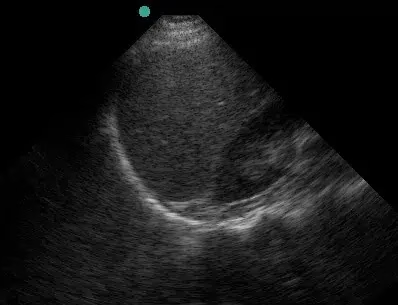

The presence of dark (black) fluid in any of these areas is presumed to be blood until proven otherwise. Identification of a fluid space between organs takes a keen eye. Evidence of fluid around the bladder suggests peritoneal bleeding or bladder rupture. The subxiphoid view also provides insight into cardiac injury, and subsequent pericardial effusion. Any evidence of fluid in any of these four locations is a positive result. Laparotomy is indicated when a positive fast is performed in an unstable patient.